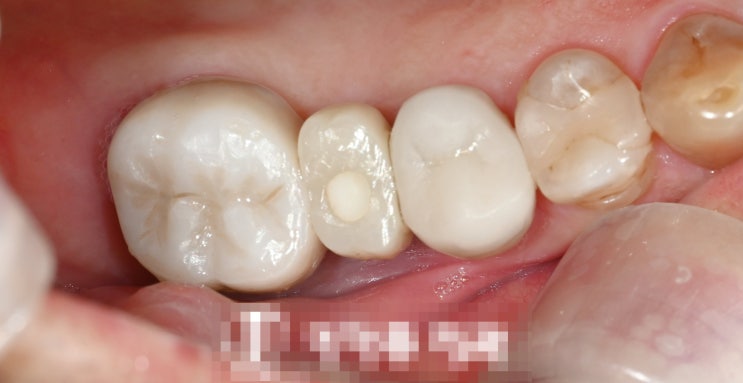

신촌역치과 정기검진의 중요성 다수의 충치 재발, 인레이, 신경치료

안녕하십니까, 대표원장 조민기입니다. 여러분들께서는 정기검진 을 받으신지 얼마나 되셨나요? 많은 분들...